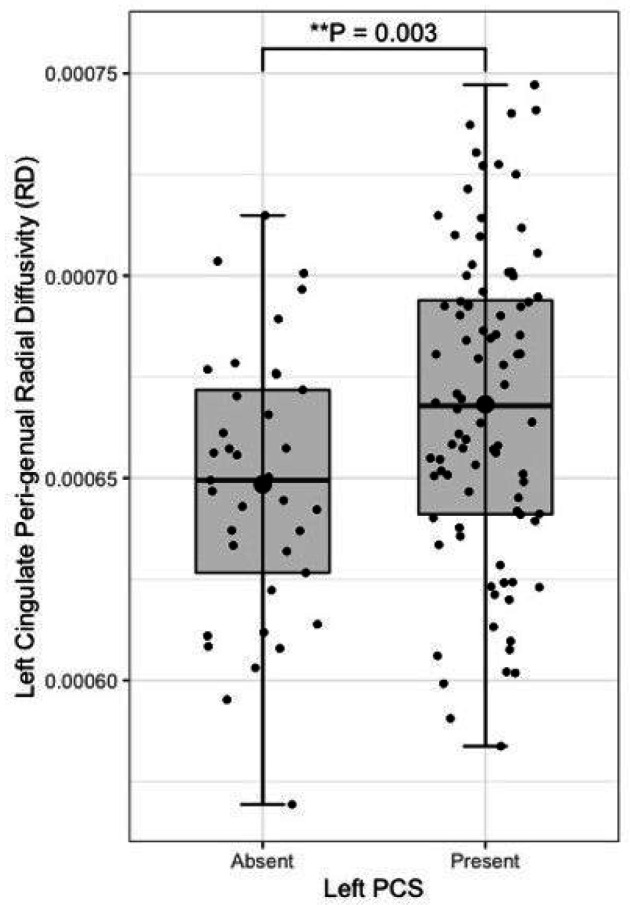

Presence of a left paracingulate sulcus was associated with reduced fractional anisotropy in the left cingulum (P = 0.02) bundle and the peri-genual (P = 0.002) and dorsal (P = 0.03) but not the temporal cingulum bundle segments. Left paracingulate sulcal presence was associated with increased left peri-genual radial diffusivity (P = 0.003) and tract volume (P = 0.012). A significant, predominantly intraregional frontal component of altered resting state functional connectivity was identified in individuals possessing a left PCS (P = 0.01). Seed-based functional connectivity in pre-defined networks was not associated with paracingulate sulcal presence.

Following quality control procedures segmentations were available for 125 subjects, (mean age 52.19, SD 5.12), see Table 1. The frequency of present to absent PCS was greater in the left (88/125) than right (71/125) hemisphere as expected. Individuals with a present left PCS displayed reduced FA of the left CG relative to individuals with an absent left PCS (β = −0.02, CI −0.01 – −0.0008 μm2/ms, P = 0.02). Using the Xtract method a present left PCS was associated with decreased FA in the ipsilateral CBG (β = −0.009, CI −0.04 – −0.008 μm2/ms, P = 0.002) and CBD (β = − 0.009, CI − 0.02 – − 0.0009 μm2/ms, P = 0.03) but not the CBT. These results are displayed in Fig. 5. Ipsilateral RD of the CBG was higher in individuals with a present left PCS compared to those with an absent left PCS (β = 2.22 ×10− 5, CI 7.58e-06-3.69e-05 μm2/ms, P = 0.003), see Fig. 6. Ipsilateral RD was similar according to PCS presence in the other studied tracts in both hemispheres.

Left PCS presence was associated with increased left CBG tract volume (β = 0.10, CI 0.02–0.18 μm2/ms, P = 0.012), see Fig. 7. Right PCS presence was not associated with right CBG tract volume. SLF-I, CG, CBD, or CBT tract volume were not associated with ipsilateral left or right PCS presence. Results are displayed in full in Table 3.

Results from the tract segmentation analyses indicate that absence of a left hemisphere PCS is associated with higher ipsilateral cingulate bundle FA. More specifically group diffusivity differences localise to the anterior portion of the cingulum; the peri-genual and dorsal cingulum bundles. Expectedly, no significant group diffusivity difference was observed in the offsite temporal division of the cingulate bundle. Furthermore, higher radial diffusivity and tract volume were observed in the left peri-genual cingulum bundle in individuals with a left PCS relative to those without. Ipsilateral tract volumes and diffusivity matrices were similar in the SLF-I between groups in both hemispheres. These results suggest that where a left PCS is present the ipsilateral cingulum bundle, specifically its anterior portions (peri-genual > dorsal) may display increased orientational dispersion. To the best of our knowledge these findings are novel and an association between gyrification and structural connectivity in healthy individuals has not previously been identified in the literature.

In the context of gyrification theories (ref. Van Essen 1997, ref. Van Essen 2020) we suggest that U-fibres, (short association fibres connecting adjacent gyri displaying a complex orientation relative to major long-white mater tracts) present in greater densities in individuals with a left PCS relative to those without may have influenced tract segment metrics. This suggestion is grounded by three principles: (1.) Inclusion of U-fibres in large tracts, referred to as a transverse inaccuracy contributes to increase the tract volume within a larger white matter tract and effect diffusivity (ref. Jbabdi and Johansen-Berg 2011). (2.) U-fibres have lower orientational coherence resulting in lower FA values. Where U-fibres are incorporated into a major tract the overall orientational coherence therefore becomes lessened resulting in a lower FA. (3.) U-fibres follow the pattern of cortical folding and as such are orientated perpendicularly to the axonal fibres of the cingulum.(ref. Movahedian Attar, Kirilina et al. 2020) U-fibre orientation and microstructure may therefore contribute to the observed increased RD in the CBP as water molecules diffuse more freely in a radial direction with respect to the CBP proper.